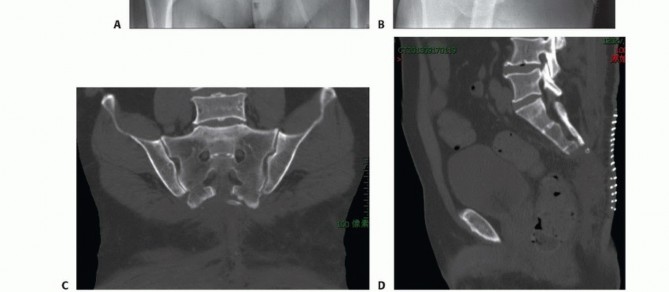

التصوير بالأشعة السينية العادية

قد تكون صور الأشعة السينية العادية غير واضحة في المراحل المبكرة من المرض. ومع ذلك، يمكن أن تساعد في تشخيص بعض الأورام، مثل الورم الحبلي الذي غالبًا ما يقع في الجزء السفلي من العجز، أو الأورام الكبيرة والمحللة تمامًا مثل ورم الخلايا العملاقة أو الكيس العظمي المتمدد في الجزء العلوي من العجز. تُعد الأشعة السينية ضرورية لإعطاء نظرة عامة ومتابعة ما بعد الجراحة.

التصوير المقطعي المحوسب والرنين المغناطيسي

- التصوير المقطعي المحوسب (CT): يُعد بتقنية التباين الوريدي الأسلوب الأمثل لتقييم مدى انتشار الورم في العظم وتدميره، والتكلسات المحتملة، والموقع التشريحي، والإمداد الدموي، وعلاقة الورم بالأعضاء الحشوية. يساعد في التفريق بين الأورام الحميدة والخبيثة.

- التصوير بالرنين المغناطيسي (MRI): بتقنية التباين، يُعد حاسمًا لتصوير الأنسجة الرخوة ومدى انتشار الورم فيها، وعلاقته بالأنسجة المحيطة (مثل الأوعية الدموية والأعصاب والعضلات والأعضاء الحشوية). يُعتبر الأسلوب الأمثل لتصوير الأنسجة الرخوة نظرًا لقدرته الفائقة على التمييز مقارنةً بالتصوير المقطعي.